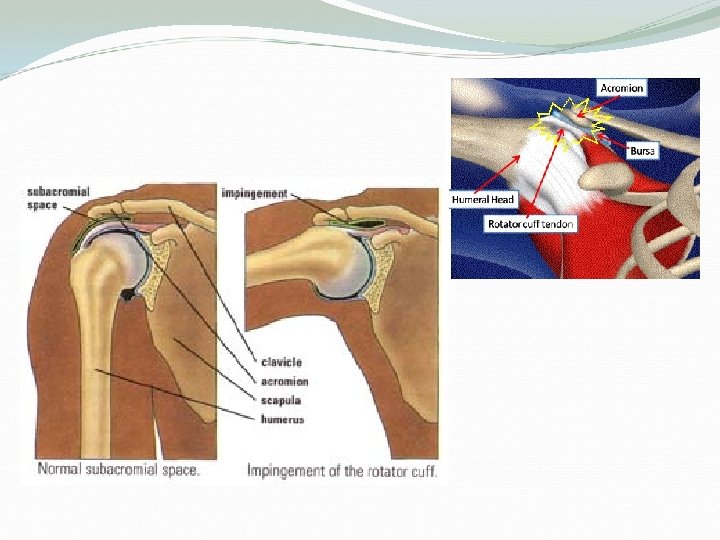

Subacromial bursa Between the acromion and the rotator cuff tendons. Protects the acromion and the rotator cuff from grinding against each other.

Impingement Syndrome Describes a condition in which the supraspinatus and bursa are pinched as they pass between the head of humerus (greater tuberosity) and the lateral aspect of the acromion